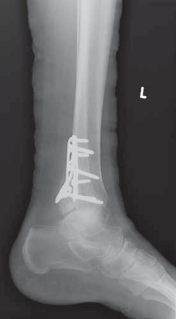

--- TECH FIG 6 • Postoperative AP and lateral radiographs demonstrating posterior plating of the tibia to buttress the posterior malleolar fracture fragment. ### TECHNIQUES